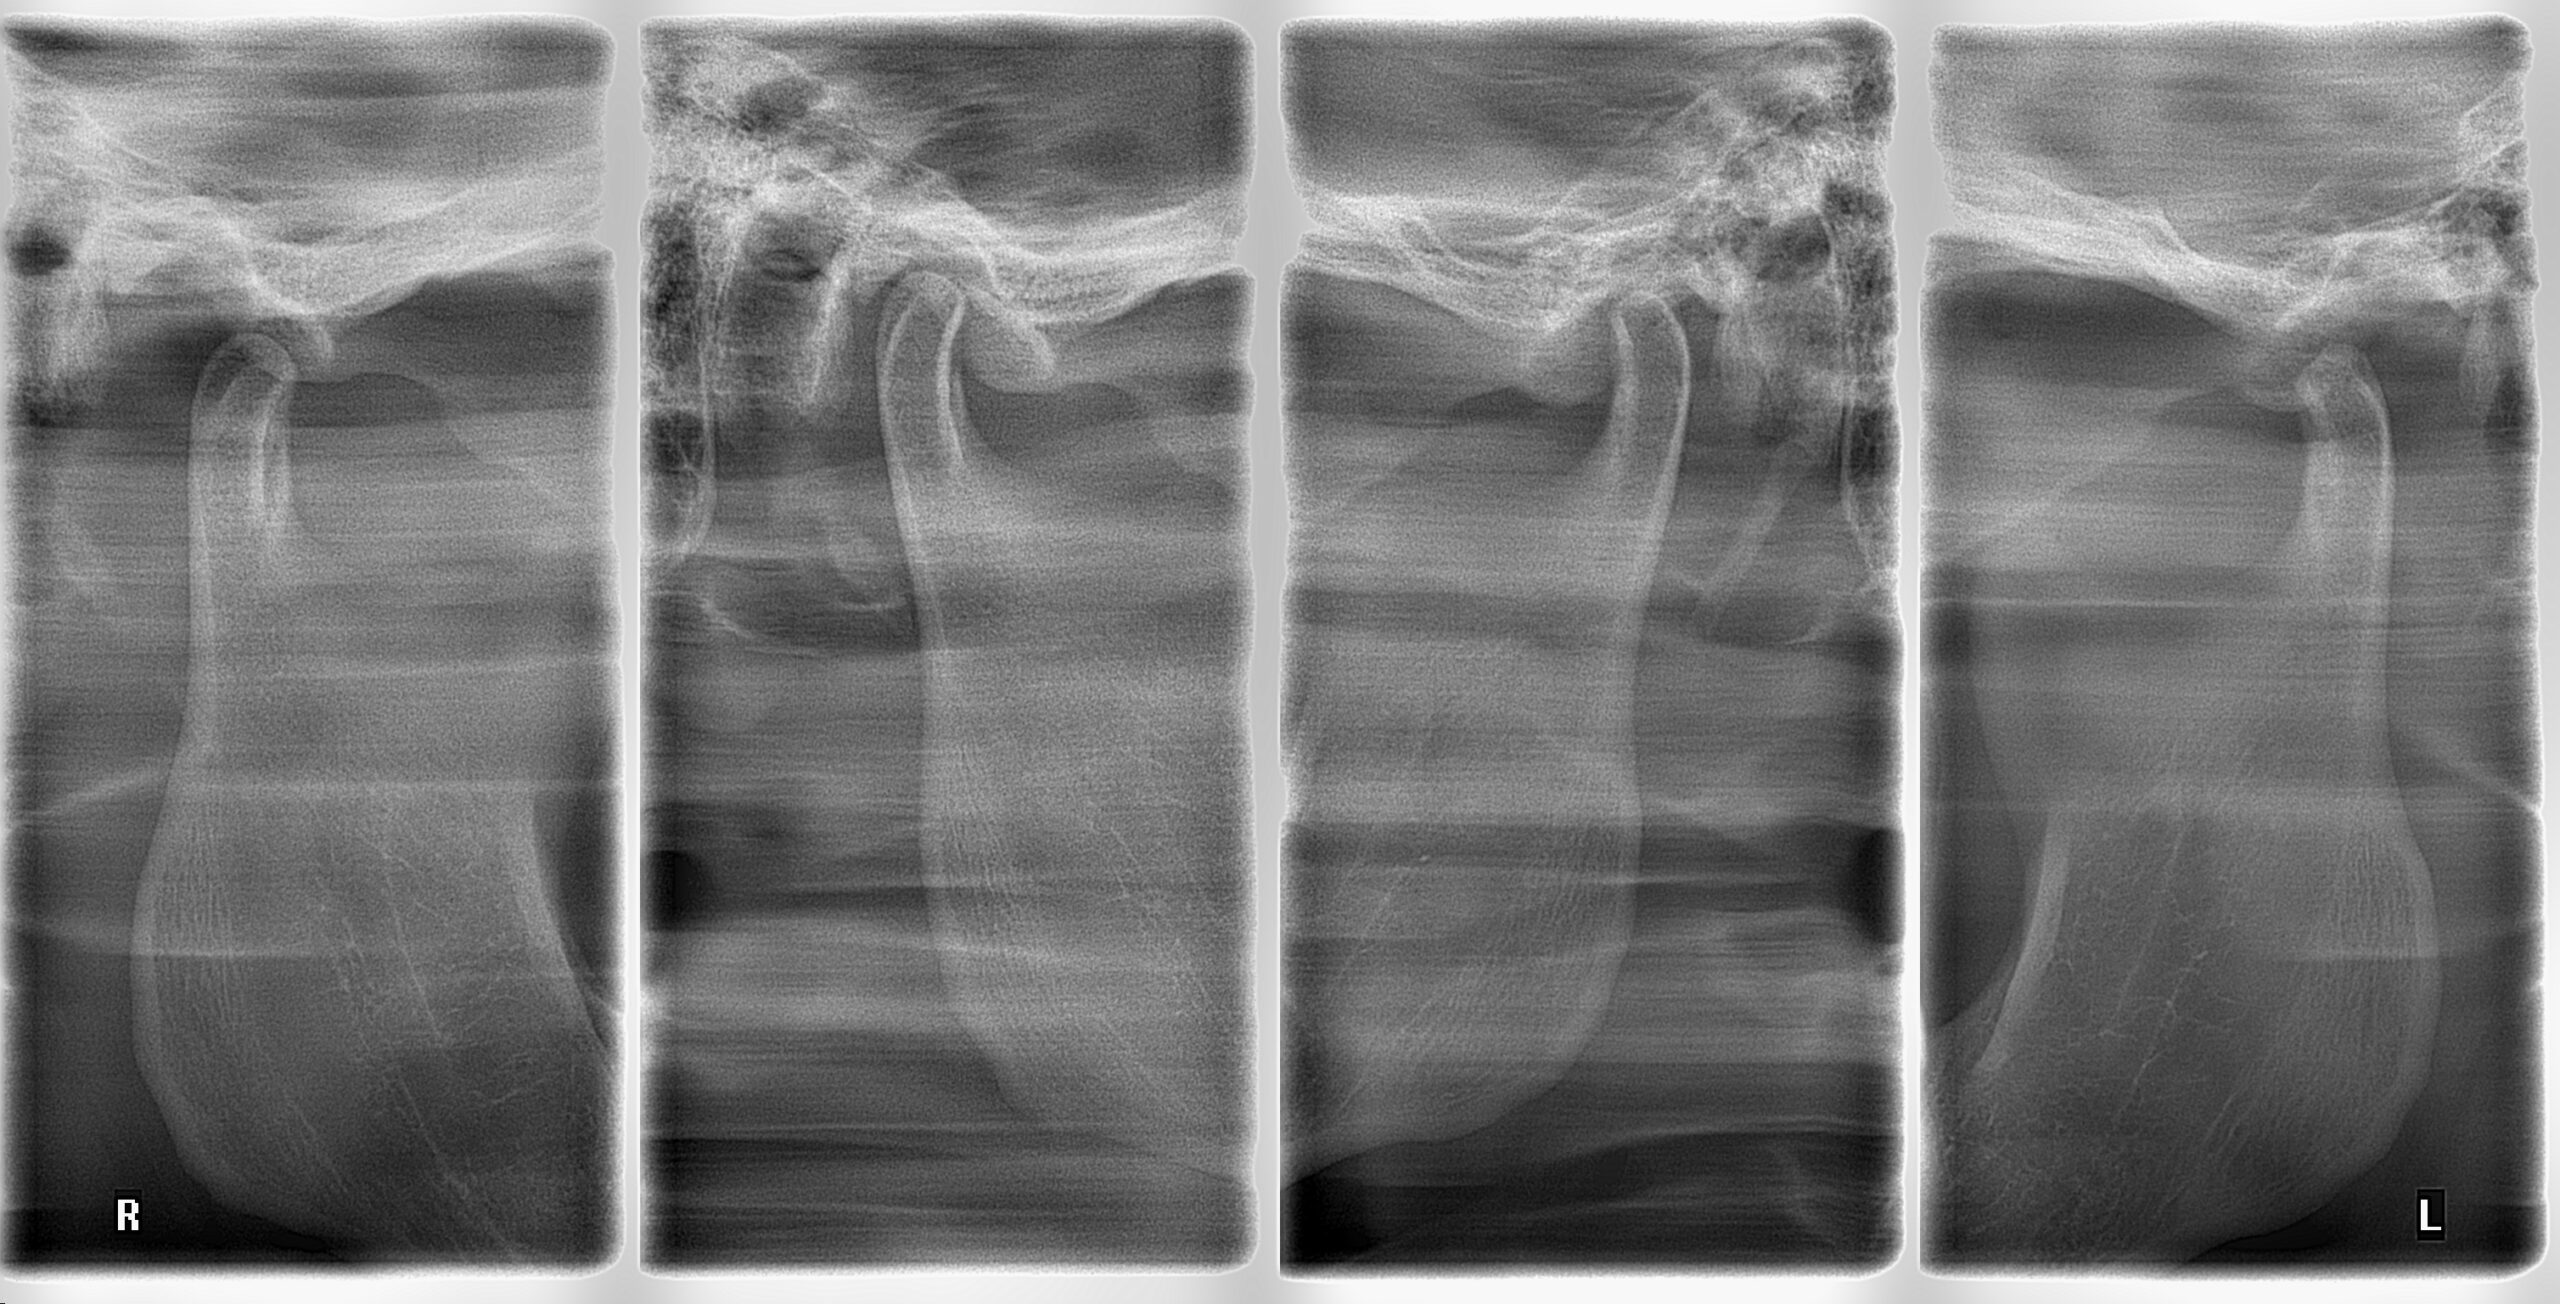

- Radiografía ATM: Radiografía específica para evaluar la articulación temporomandibular, la función y morfología de los cóndilos mandibulares y observar alteraciones óseas a nivel articular.

Se evalúa la morfología, función, alteraciones óseas y estado de los cóndilos mandibulares mediante radiografías específicas de ATM.